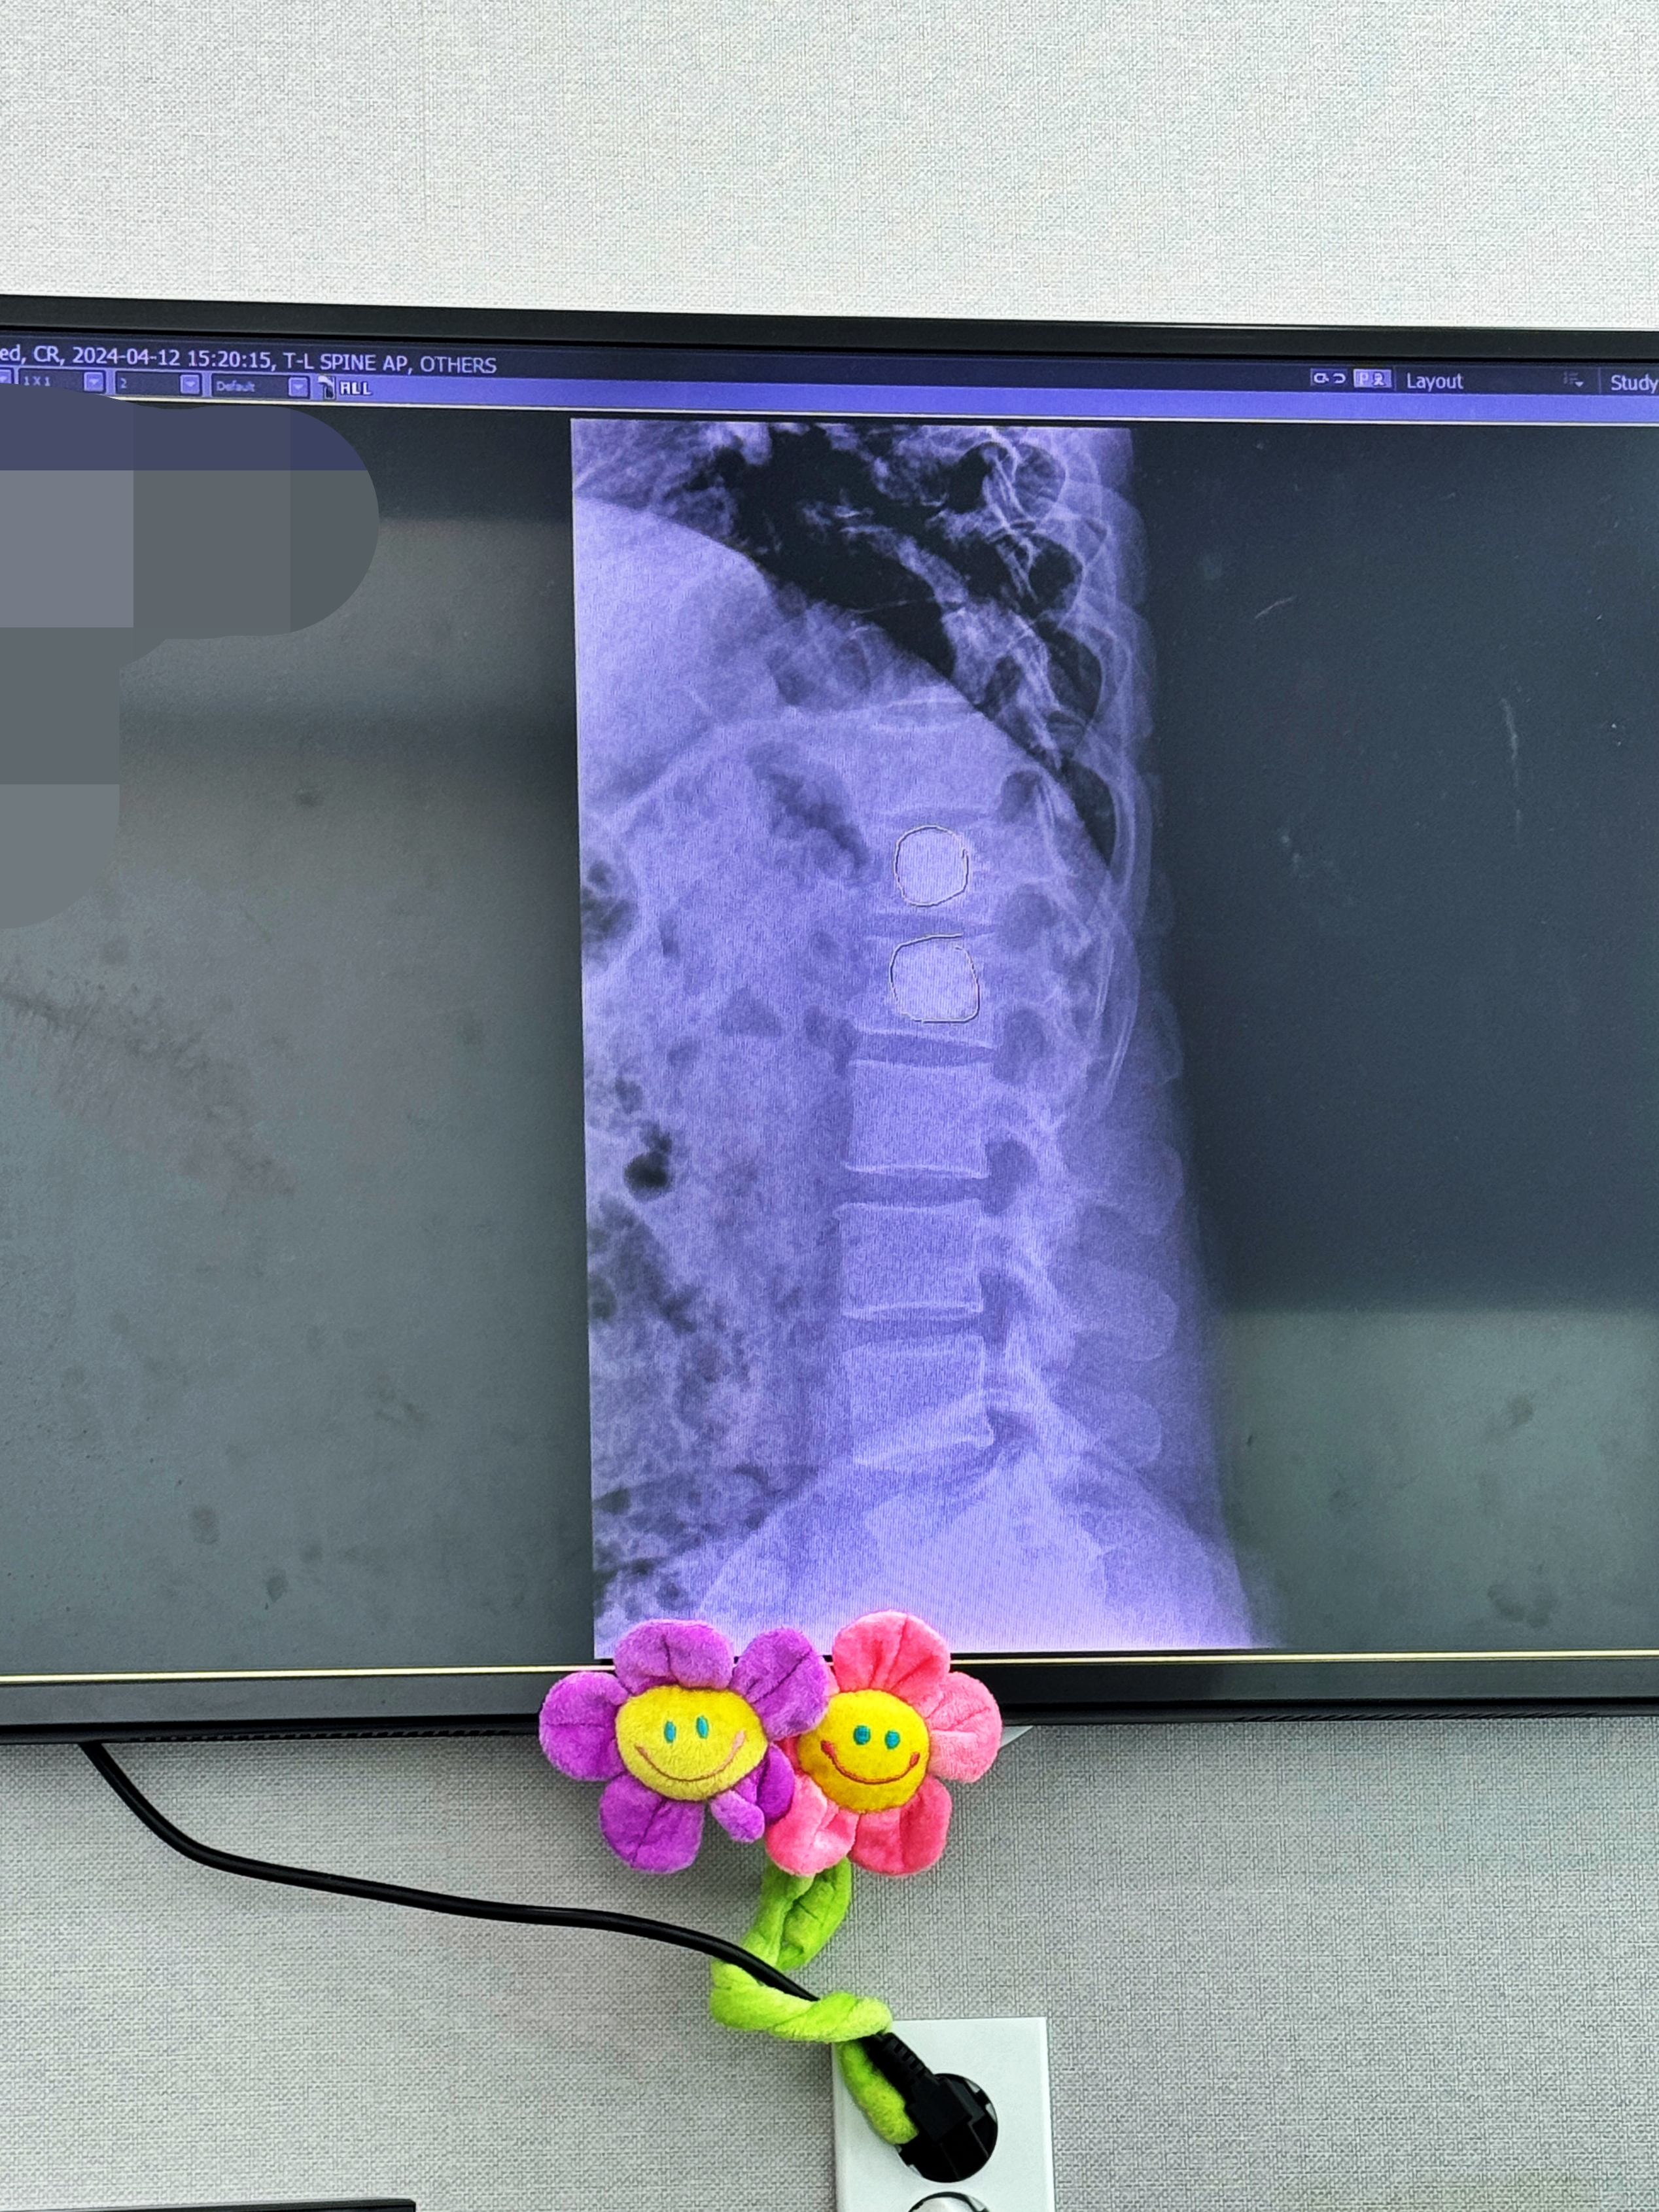

모니터에 보이는 X-RAY상에 동그랗게 표시한 부분이 골시멘트입니다.

넣을때는 좀 아팠지만 수술 다음날 일어나니 거짓말처럼 뼈에서 느껴지는 통증은 사라졌습니다. 다행히 경과도 좋고 일상생활에서 느껴지는 통증이 있는지 물어보시는데 일상생활에 지장이 없고 가끔 아프다 안 아프다 한다고 하니 무거운 물건만 들지 말고 당분간 조심하면 일을 해도 상관 없을 것 같다고 하시네요.